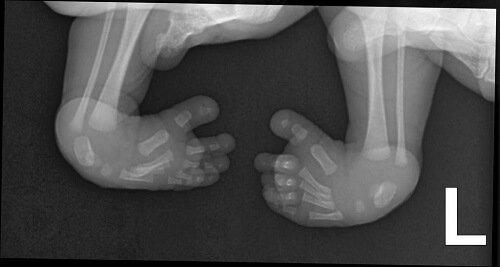

Mặc dù chân khoèo có thể quan sát được bằng mắt thường, việc sử dụng kỹ thuật chẩn đoán hình ảnh sẽ giúp các bác sĩ nắm được cụ thể tình hình, từ có có hướng điều trị phù hợp.

Kỹ thuật X-quang được sử dụng phổ biến. Tùy theo mức độ dị tật cũng như các yếu tố liên quan mà khả năng tiến triển của bệnh sẽ khác nhau đối với từng trường hợp. Nếu chân khoèo kèm theo tình trạng bị biến dạng xương ở bàn chân thì sẽ rất khó khăn trong việc chỉnh hình lại bàn chân. Bên cạnh đó, nếu các cơ của bàn chân có dị thường thì khả năng tái phát cũng rất cao sau khi được nắn chỉnh.